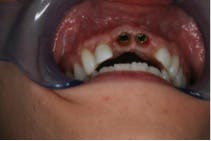

The oral surgeon, Dr. Richard Kim, D.D.S., M.D., explained how the procedure went. “When the patient first came in, she was put to sleep with intravenous general anesthesia. When she was asleep, I removed teeth numbers eight and nine. For immediate extraction with implant placement, the first initial pilot hole is placed a little bit lingually from the extraction site. You want the top of the implant to come out where the tooth cingulum would be so that more porcelain can be placed toward the buccal of the crown. After this, you go in with a 2-millimeter wide twist drill, then a larger tapered twist drill, and keep increasing the diameter of the drill until you reach the desired size, which was 4.3 mm in this case. I used Tapered Groovy Titanium Nobel Biocare implants for the patient at a size of 4.3 mm in diameter. The implants had threads which made it a little wider so it could engage the bone. I then used a torque wrench to tighten the implant into the bone and I was able to obtain a force of 45 Ncm2, which tells you the primary stability of the bone. I then placed bone allograft, which included BMP-2, to promote bone regeneration. The last step was securing the healing abutments, suturing up the tissue, and adjusting the flipper to fit.” (Refer to figure 4.)

As previously stated, the gingival flap performed on the patient during the implant surgery resulted in blunted papillae on all four of the maxillary incisors, revealing one millimeter of cementum on the lateral incisors and shrinking the tissue making the healing abutments visible over the flipper. Composite was added to the apical portion of the flipper to mimic tooth structure and conceal the abutments (refer to figure 5).